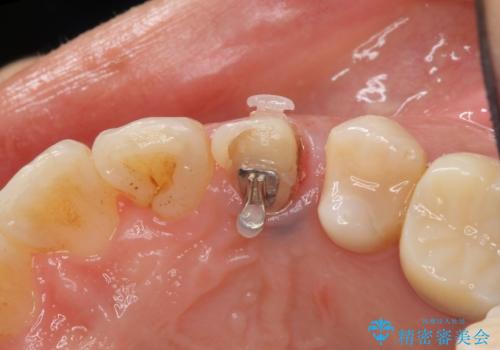

治療途中

左:虫歯を除去したところ。遠心が歯ぐきより深い状態です。中:そのままかぶせようとすると、遠心が歯ぐきが腫れやすい状態です。右:エクストリュージョンをしたことで、遠心の歯ぐきの腫れが収まっていることがわかります。